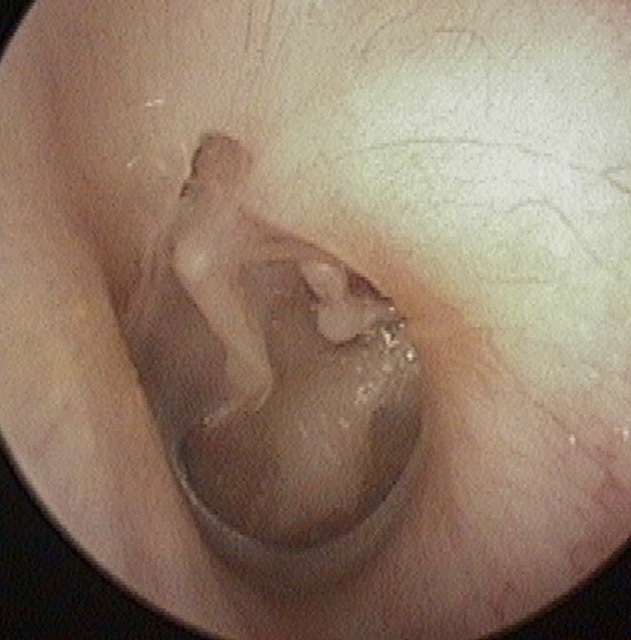

Perforation